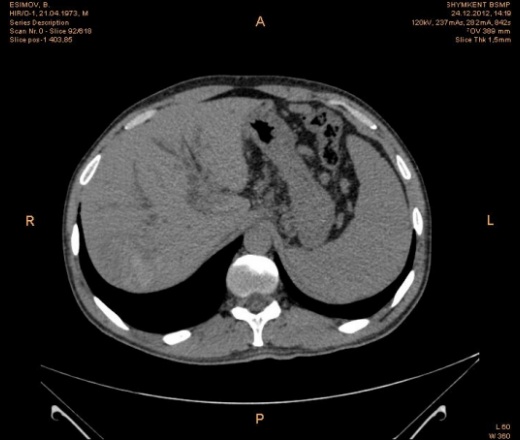

Предварительно образование головки ПЖ, и в печени. Что с ферментами?

на операций рак головки подж.железы с метастазир. печень.

инфильтрация тут нисходящей 12 перст кишки , расширенного холедох,расширенный вирсунгов проток ,нижная граница очень близко прилежит к нижней полой вене с правой почечной веной ,но четко визуализирутся передний листок фасции Героты(нельзя исключить ее инфильтрацию), инфильтрация конгломератом увеличенных лимфатических узлов ворот печени портальной вены с варикозным расширением вен, на вышележащий срезах четко определяются верхняя брыжеечная вена и артерия ,не хватает срезов для полной визуализации(помогли бы мпр),инфильтрирована восходящая ободочная кишка,конгломерат лимфат узлов за головкой поджелудочной железы в виде гиподенсивного участка вытянутой формы , ,мтс в печень,парааортальные